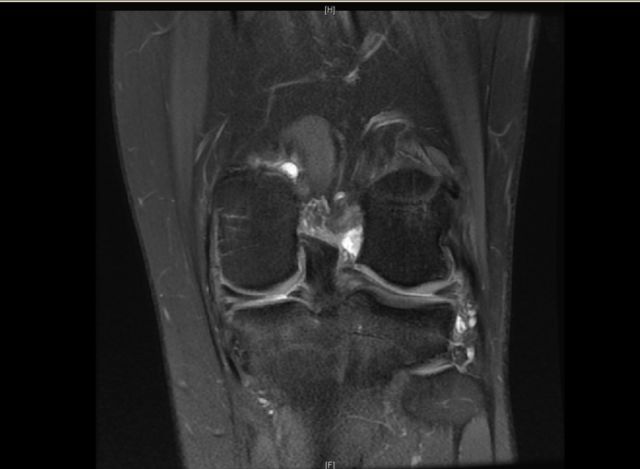

前交叉韧带断裂

从这个病例我们可以看到明显的股骨外髁骨擦伤,韧带的形态是中断的,大片的渗出病变,并且以胫骨平台的夹角变小,下止点可见部分信号增高,上止点可见大片的渗出病变,缺乏韧带止点应有的形态和张力,轴位片也可以看到内外上止点信号改变。所以这个病例考虑前交叉韧带断裂。